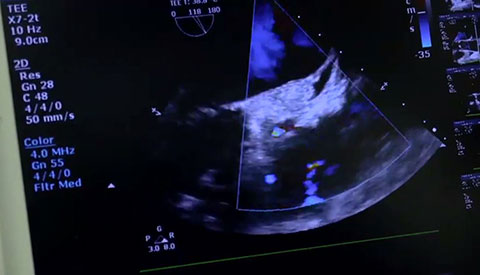

تم تشخيص أحد المرضى لديك بتضيّق في الصمام الأورطي المصحوب بأعراض. يبلغ عمر المريضة 85 عامًا وهي تعاني من السكري وارتفاع ضغط الدم. أنت تدرك خطورة وضعها الصحي ما يجعلها غير مناسبة لجراحة القلب ولكن يسمح لها بأن تكون مرشحة لاستبدال الصمام الأورطي باستخدام القسطرة (TAVR). في يومنا هذا، تمنح حلول التصوير المبتكرة والأجهزة التي تعمل عن طريق الجلد الأمل لبعض المرضى الذين لا تتوفر لهم حتى الآن أي خيارات علاجية أخرى.